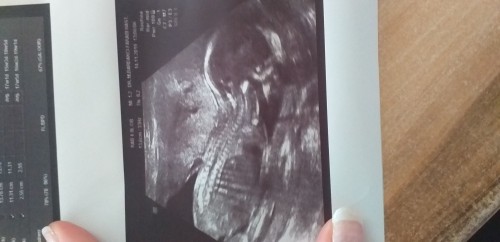

Kızlar bugün kızım olacağını öğrendim ❤

image

Canım tam gördüm  doktor bacak arası üç çizgiyi :) hayırlı olsun bu arada cnm,ilk çocuk mu?

Evet ilk :) gördüm evet kız

Evet :D burda yanlış bilmişler sürekli gittigim doktor yanılma payı falan yok dedi

Aynen değişti 12 de kendi doktorum kıza benziyor dedi sonra devlete gittim %99 erkek dedi dün kendi doktoruma yine gittim %100 kız dedi yanılmışlar kordonu pipi sanmışlar dedi gösterdi de hiç birşey yok  :D